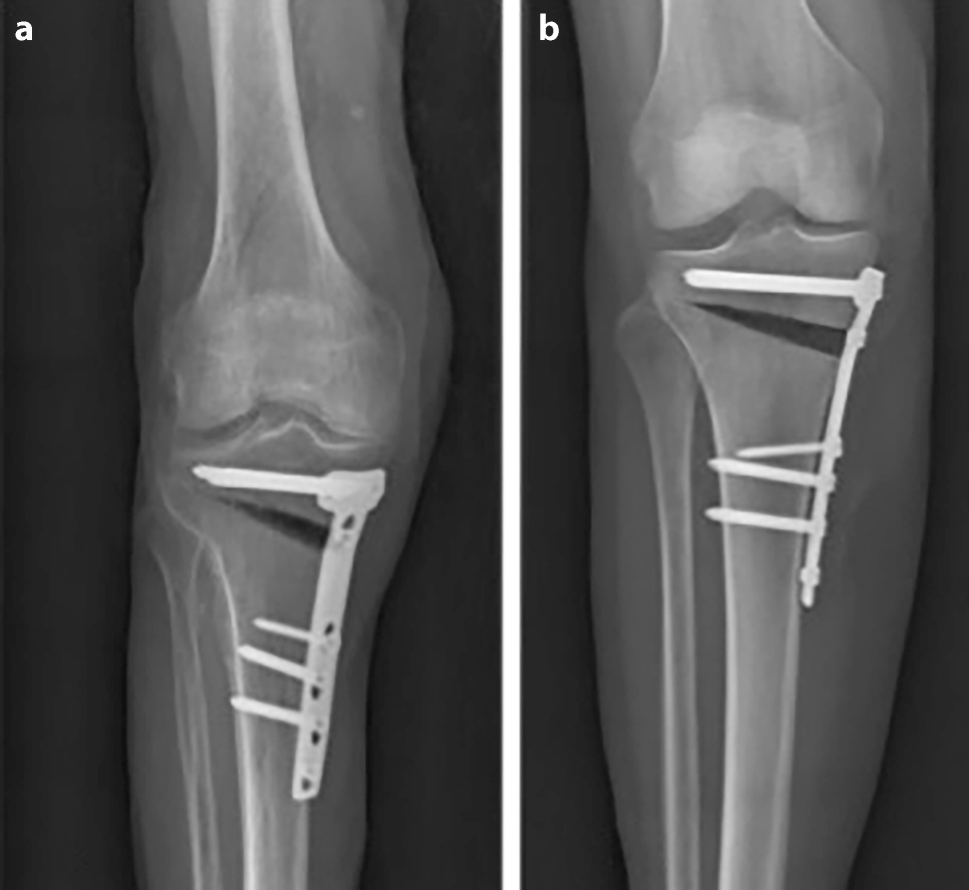

Radiological parameters were measured by one specialist (orthopedic surgeon) as follows: in the CT scans, the position of the plate was determined in the axial images by measuring the rotational offset of the plate referring to the tibial tuberosity as 0° (see Fig. 1). The medial osteotomy width, tibial slope and osteotomy slope were measured on the X rays. Furthermore, the representation of the osteotomy was evaluated by judging the bony overlap of the osteotomy borders into the osteotomy gap (yes/no) at different degrees of flexion.

Fig. 1

Measurement techniques on length of osteotomy (blue line) and medial osteotomy width (black line) are displayed in picture a; measurement technique of tibial slope and osteotomy slope (blue lines) are shown in picture b. In axial CT sequences, rotational offset of the plate (referring to the tibial tuberosity) was measured (red lines) (c)

To establish exact representation of the osteotomy gap, a strict side profile view of the plate was achieved by internal rotation of the leg as well as flexion of the knee to compensate for the posterior slope of the tibia and the osteotomy itself (see Fig. 4). Best results were obtained with 30° of flexion (see Table 1). The mean osteotomy width was 12.5 mm (range 10.7–13.9 mm). The mean tibial slope was 10.3° (range 7.4–17.2°) and mean osteotomy slope was 17.2° (range 9.2–22.7°). The internal rotation offset of the plate measured in the axial CT scans showed a mean value of 25° (range 15–31.5°). The overlap of the tibial tuberosity is an obstacle for the evaluation of ossification in the central part of the gap, which can be overcome in the CT analysis (see Fig. 5). The CT scan was able to erase most of the metal artefacts and trabecular structure could be additionally displayed.

Fig. 4

a The conventional AP radiography of the cadaveric leg shows tibial overlap of the posterior tibia in the gap (b) exact representation of the osteotomy gap is achieved with 20° of internal rotation and 30° of flexion in the knee joint